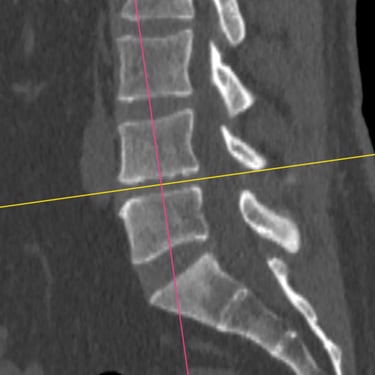

El síndrome postdiscectomía se presenta cuando persiste o reaparece el dolor lumbar y radicular después de una cirugía previa de hernia discal. Puede estar asociado a inestabilidad segmentaria, fibrosis epidural o degeneración discal progresiva. Cuando el manejo conservador no logra aliviar los síntomas, la fusión intersomática transforaminal (TLIF) mínimamente invasiva constituye una alternativa eficaz. Este procedimiento permite descomprimir las estructuras nerviosas, restaurar la altura discal y estabilizar el segmento afectado con menor daño muscular. La técnica mínimamente invasiva favorece menor sangrado, recuperación más rápida y mejores resultados funcionales.